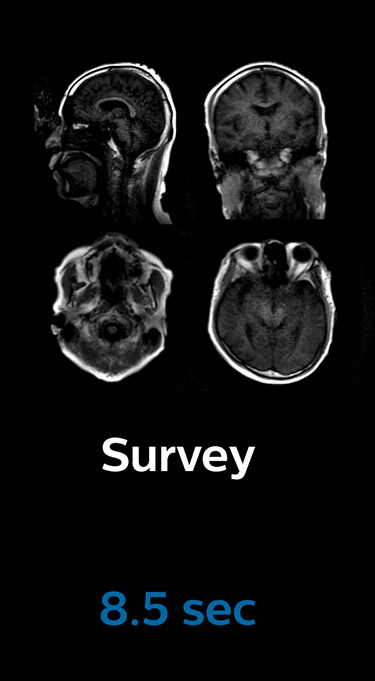

Fast MRI of brain

With Compressed SENSE, the scan time for the routine brain examination at KNC was reduced from 15:48 to 10:19 minutes, which corresponds to 35% reduction.

Brain without Compressed SENSE

Brain with Compressed SENSE

Ingenia 3.0T CX

Scan time 15:48 min.

Scan time 10:19 min.